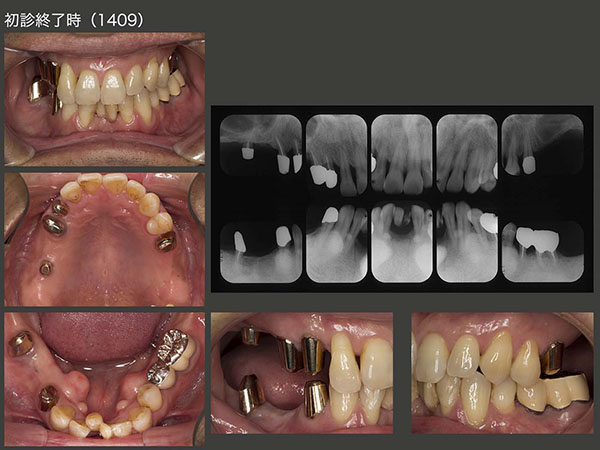

2014年9月,初診終了時の状態.片側処理の可撤式義歯を合計3個装着した.支台歯の歯周ポケットは3mm以下に改善したが,予後が心配な歯であることに変わりはない.そこで,清掃性が良く,将来の変化に対応しやすいコーヌス義歯を採用することにした.左下も可撤式にしたかったが,経済的な負担も大きくなるので,左下5,6は,クラウンで連結固定した.下顎前歯は,ここで咬まないということを条件に,抜去した歯を単に接着剤(スーパーボンド)で隣在歯と固定した.また,みるからに咬合力が強いと思われることから,意識して咬み過ぎないように,さらに日中の咬みしめ(TCH)に特に注意するよう指導した.

コーヌス義歯装着時.片側遊離端欠損症例には通常2本の支台歯が必要となる.(中・側切歯は含めず.)したがって,左上にも2本の支台歯が必要となる.今回は左上4がバージントゥースであることから,審美的には良くないが,歯を削去しないですむクラスプを用いた.なお,欠損部から2本目の支台歯の目的は,1本目の支台歯に加わる側方力を減らすことであると私は考えている.

初診時および初診終了時のパノラマX線写真の比較.保存不可能な歯の抜去を4本,ヘミセクションを2本行った.自然挺出を行った右上3および左下5の歯周ポケットが改善したことから,本来人間の持つ自然治癒力の高さに驚かされた.